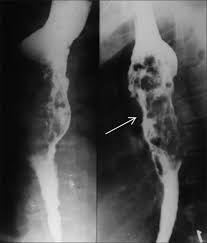

Clinical guidelines of the russian gastroenterological association. Esophagitis refers to inflammation of the esophagus. Behr j, kreuter m, hoeper mm, wirtz h, klotsche j, koschel d, andreas s, claussen m, grohé c, wilkens h, randerath w, skowasch d, meyer fj, kirschner j. Peptic strictures cause a gradually progressive dysphagia for solid foods. Department of radiology of the loyola university medical center, usa. Epidemiology the actual incidence and prevalence of idiopathic esophagitis of hiv are unknown. Hsv esophagitis has been described in immunocompetent hosts, however, it remains a rare entity. Esophagitis due to herpes simplex virus (hsv) infection1,2. Cobblestone esophagitis (эзофагит со слизистой булыжной мостовой). Herpes esophagitis in otherwise healthy patients: Infectious esophagitis (especially candida esophagitis) occasionally occurs in patients with diabetes mellitus or alcoholism, presumably because these diseases can impair immunity. ( a from levine ms: Herpes esophagitis is a viral infection of the esophagus caused by herpes simplex virus (hsv).

Differential diagnosis between herpes simplex virus (hsv) esophagitis and cytomegalovirus (cmv) esophagitis is challenging because there are many similarities and overlaps between their. Herpes esophagitis in healthy adults and adolescents: B from levine ms, woldenberg r, herlinger h, et al. Healing and relapse of severe peptic esophagitis after treatment with omeprazole. Candida and herpes simplex virus (hsv) esophagitis has been reported in 2% to 4% in immunocompromised patients.

Epidemiology the actual incidence and prevalence of idiopathic esophagitis of hiv are unknown. Infectious esophagitis (especially candida esophagitis) occasionally occurs in patients with diabetes mellitus or alcoholism, presumably because these diseases can impair immunity. Canalejo castrillero e, garcía durán f, cabello n, garcía martínez j. Animals with mild esophagitis generally have a favorable prognosis. Hiv esophagitis is a possible cause of odynophagia in immunosuppressed patients with hiv. Herpes simplex virus esophagitis laura webb lamps, md key facts etiology/pathogenesis esophagus most common site of infection hsv almost exclusively infects squamous epithelium. Before the availability of combination antiretroviral therapy (cart). A recent review reveals 56 documented cases in the literature. The relationship between hiatus hernia, reflux and reflux esophagitis is controversial and poorly understood. Diagnostics and treatment of infectious esophagitis: Herpes esophagitis in healthy adults and adolescents: Healing and relapse of severe peptic esophagitis after treatment with omeprazole. Esophagitis due to herpes simplex virus (hsv) infection1,2.